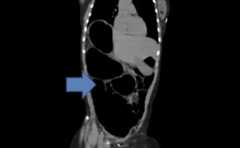

Coronal image of the contrast-enhanced CT of the abdomen showing a significantly distended sigmoid colon

Coronal image of an abdominal contrast-enhanced CT showing a significantly distended sigmoid colon looped in an inverted “U” without haustral markings

Image: “CT of the Abdomen” by Department of Medicine, New York-Presbyterian Hospital, Weill Cornell Medical College, New York City, NY, USA. License:CC BY 3.0